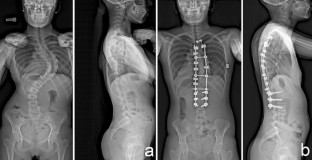

Adolescent idiopathic scoliosis treated with posteromedial translation: radiologic evaluation with a 3D low-dose system

Computed tomography can be used for three-dimensional (3D) evaluation of adolescent idiopathic scoliosis (AIS) patients, but at the expense of high radiation exposure, and with the limitation of being performed in the supine position. These drawbacks can now be avoided with low-dose stereoradiography, even in routine clinical use. The purpose of this study was to determine the 3D postoperative correction of AIS patients treated by posteromedial translation.

Forty-nine consecutive patients operated for AIS (Lenke 1–4) using posteromedial translation were included. Corrections were evaluated preoperatively, postoperatively and after at least 2 years using the EOS imaging system. 3D angles were measured in the plane of maximum deformity.

Mean number of levels fused and operative time were 13.5 ± 1 and 215 ± 25 min, respectively. Main thoracic, proximal thoracic, and lumbar curves corrections averaged 64.4 ± 18, 31 ± 10 and 69 ± 20 %, respectively. Mean T4–T12 kyphosis increased 18.8° ± 9° in the subgroup of hypokyphotic patients. Mean apical vertebral rotation reduction was 48.3 ± 20 %. Trunk height gain averaged 27.8 ± 14 mm. There was no pseudarthrosis or significant loss of correction in any plane during follow-up. Two patients (4 %) developed asymptomatic proximal junctional kyphosis, despite having normal thoracic kyphosis. Their sagittal balance was shifted posteriorly by 36 and 47 mm, respectively, by the operation, but revision surgery was not performed.

Low-dose stereoradiography provided 3D reconstructions of the fused and unfused spine in routine clinical use. Postoperative 3D analysis showed that posteromedial translation enhanced sagittal balance correction, without sacrificing frontal or axial correction of the deformity.

Fig. 1